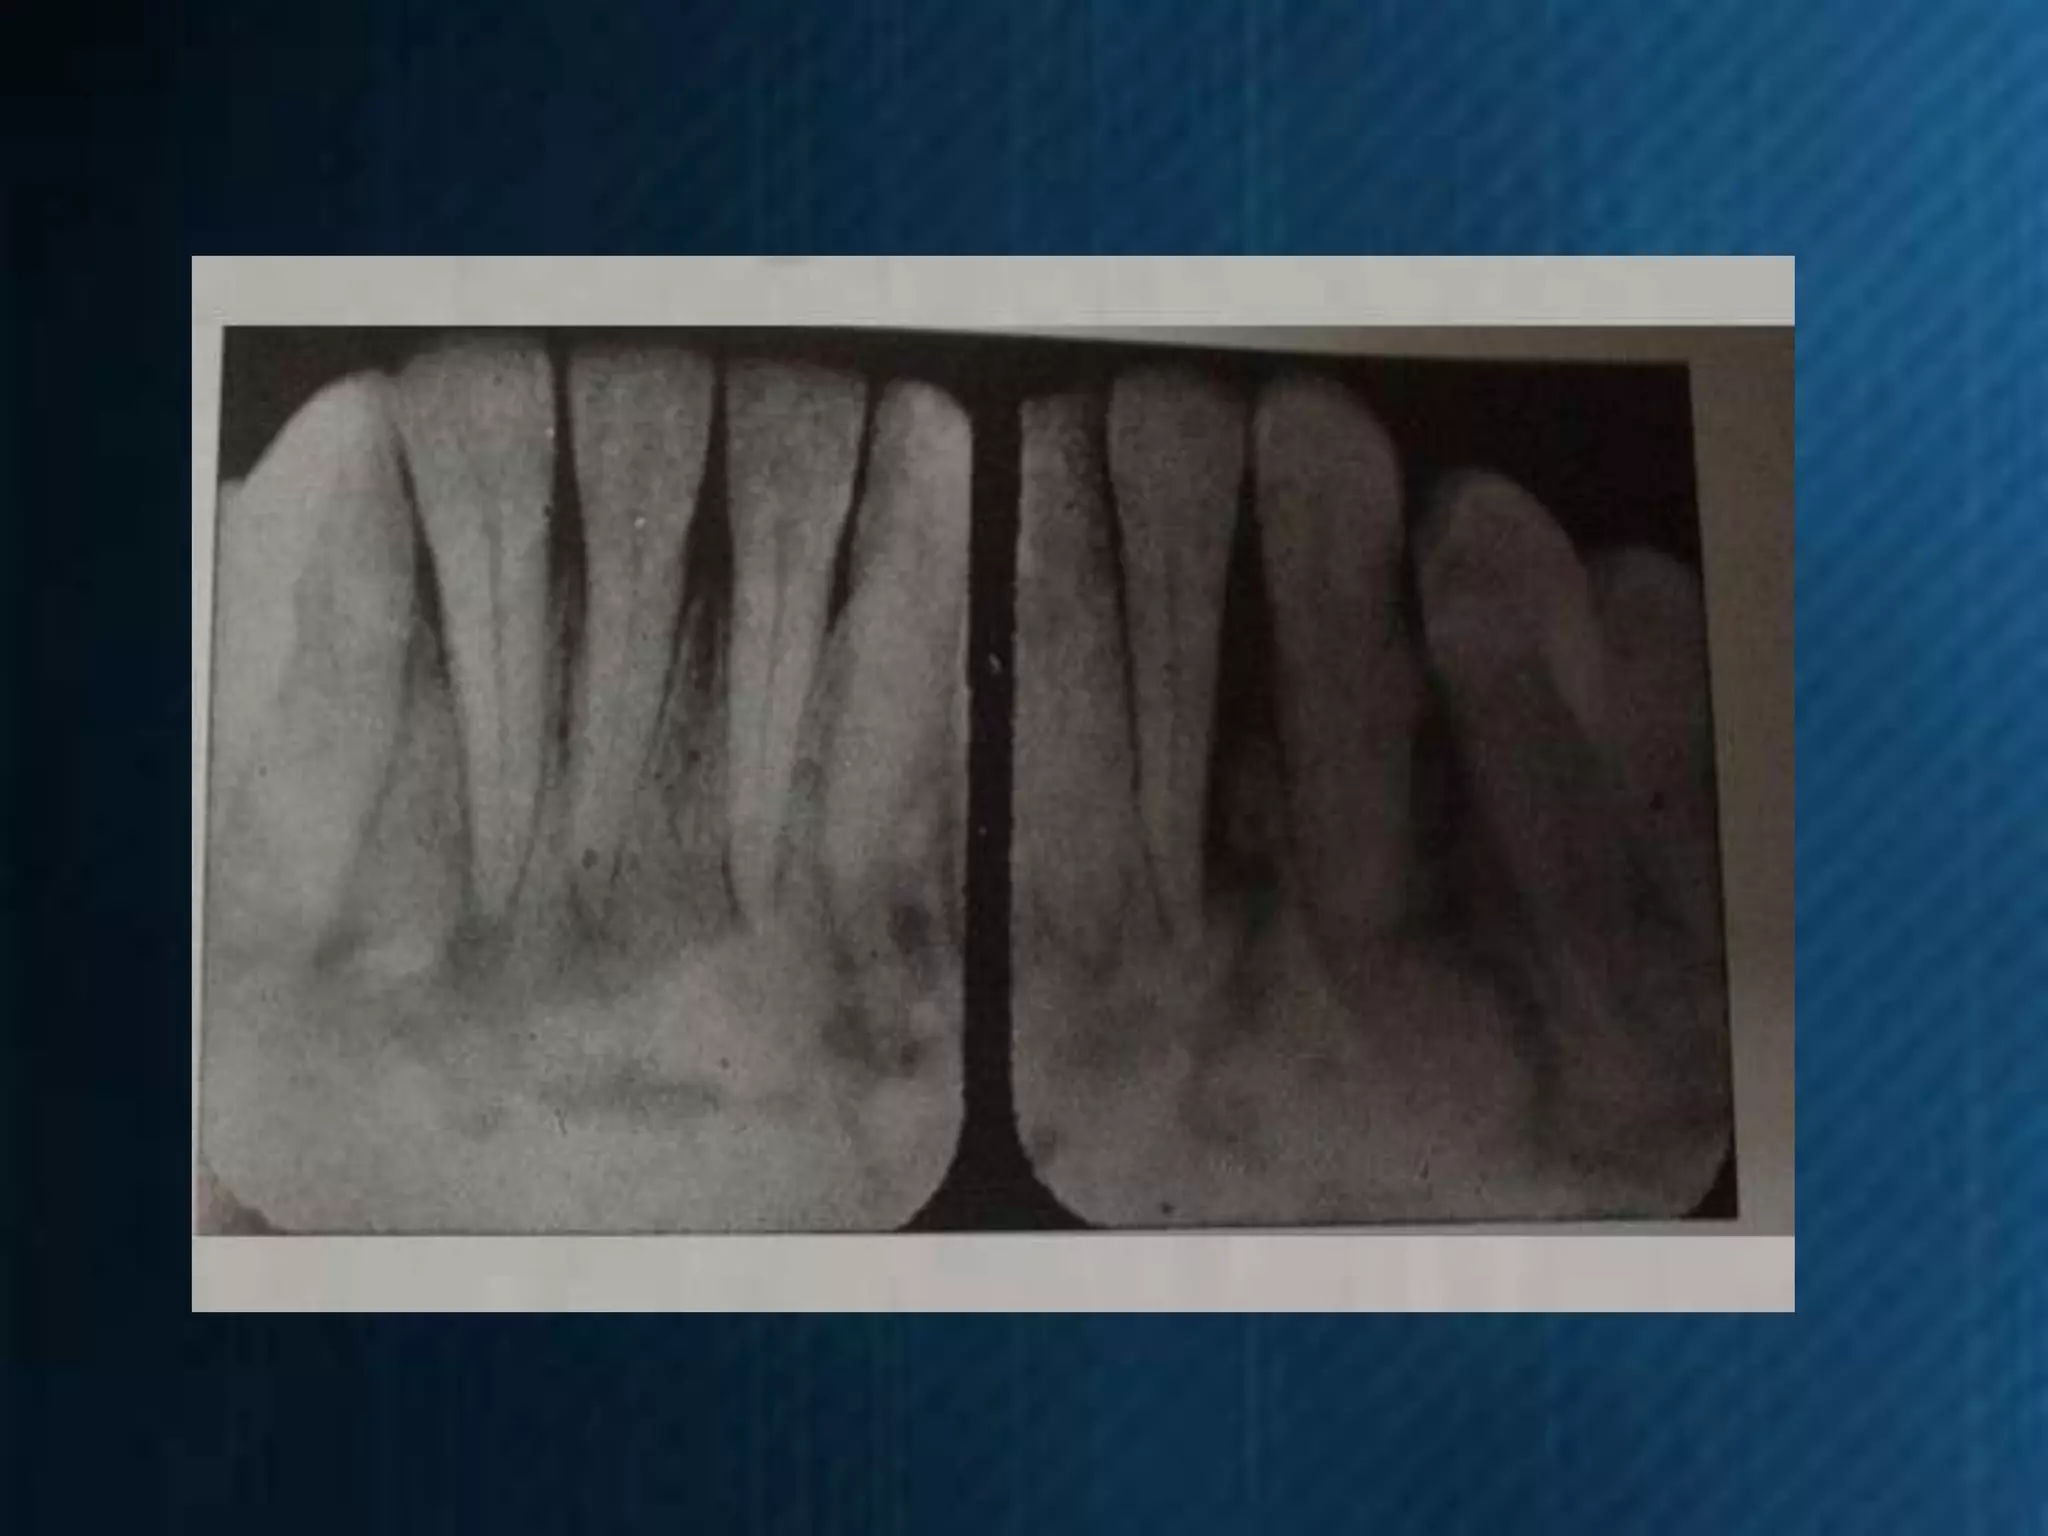

Ejercicios de

Interpretación

Radiográfica